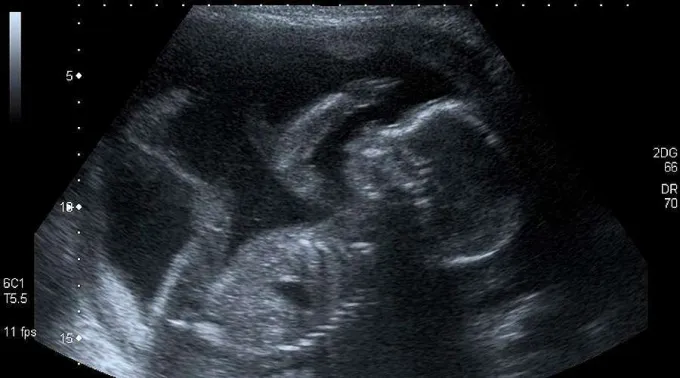

Um estudo da University College London descobriu que os golpes que os bebês dão dentro do ventre materno, entre os quais os chutes, e outros movimentos, os ajudam a desenvolver seu cérebro e reconhecer as partes de seu corpo.

As mães podem começar a sentir os golpes de seus bebês a partir da 16ª semana de gestação, embora alguns movimentos espontâneos começam às sete semanas.

Segundo indicou LiveSciense, o estudo sugere que, com cada golpe ou chute – conhecidos como movimentos fetais –, o bebê constrói uma rede cerebral básica que lhe permite entender qual parte do corpo está se movendo e como se toca.